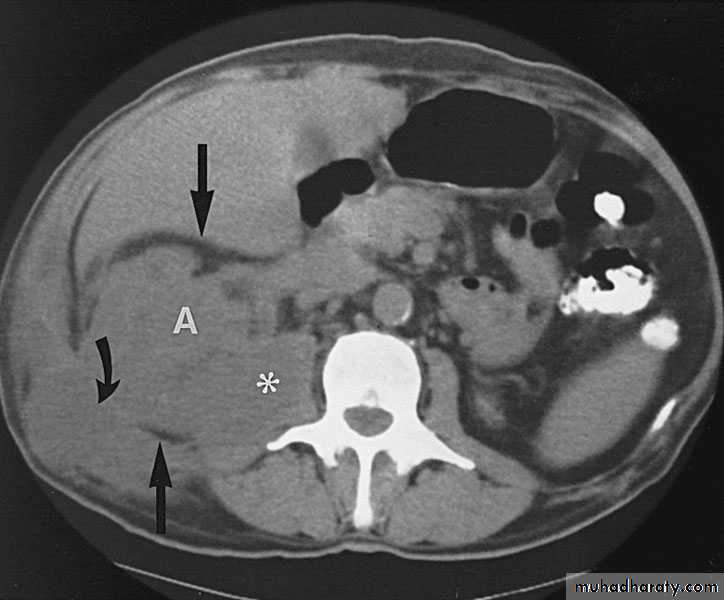

Perinephric Abscess

Route of infection:Rupture of renal abscess

Infected perinephric hematoma or urinoma

Extension from nearby organs: Appendix, Gall Bladder, Pelvic organs.

Hematogenic: Tonsillitis, boils etc.

Pathology

Cortical abscess coallese, enlarge, rupture to the perinephric space, form a perinephric abscessFluid filled inflammatory mass

Thick wall, adhesions.

Clinical picture

Fever , rigor

Dysuria, frequency

Renal tenderness

Visible loin mass, tender, +ve fluctuation

Investigations

Leucocytosis, AnemiaPyurea, +ve bacterial culture

U/S

CT scan

KUB : soft tissue mass, stones.

IVU , Tomography

Chest x ray : ? Reactionary pleural effusion